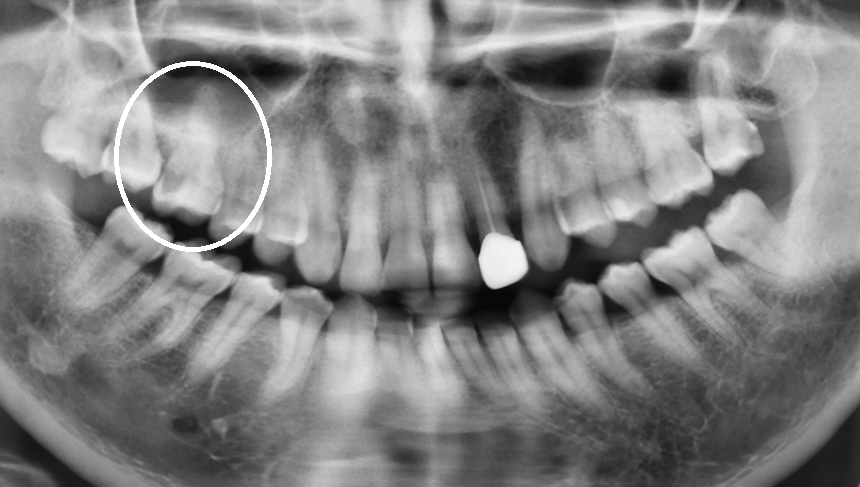

術前X光片